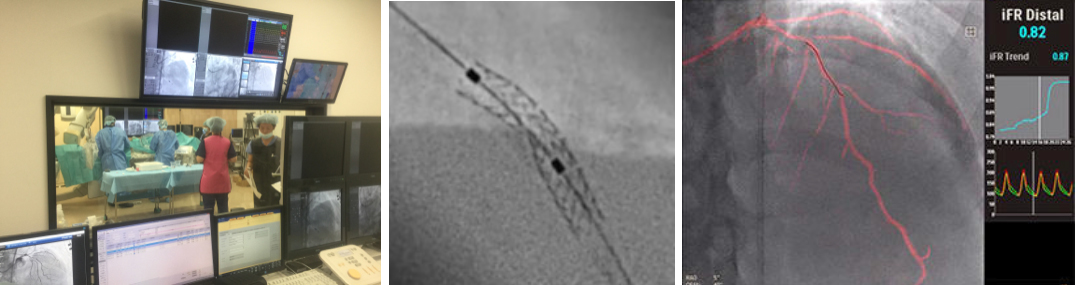

カテーテル検査・治療

カテーテル室では、冠動脈ステント治療をはじめ下肢動脈やシャント血管の治療、ペースメーカー植え込み治療、心臓電気生理検査およびカテーテルアブレーション治療などが行われます。